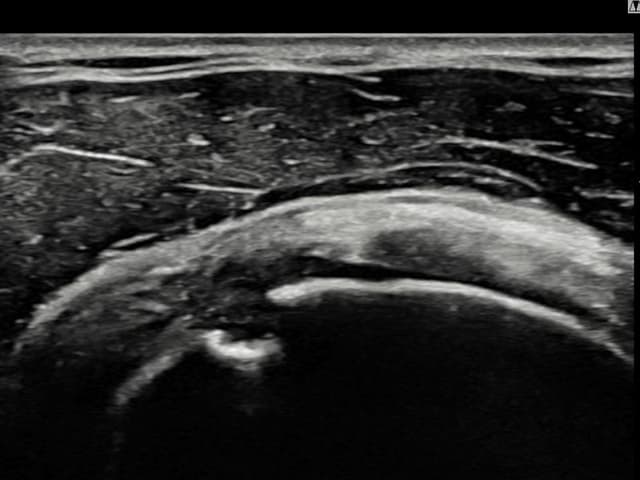

[経過期間: 23.09.19~23.11.21]

[縫縮術] 超音波検査にて右 棘上筋腱 関節面側部分断裂(9mm × 4mm (腱厚の約38%欠損))を確認。縫縮術施行後、腱の連続性が回復し、日常生活に復帰されました。